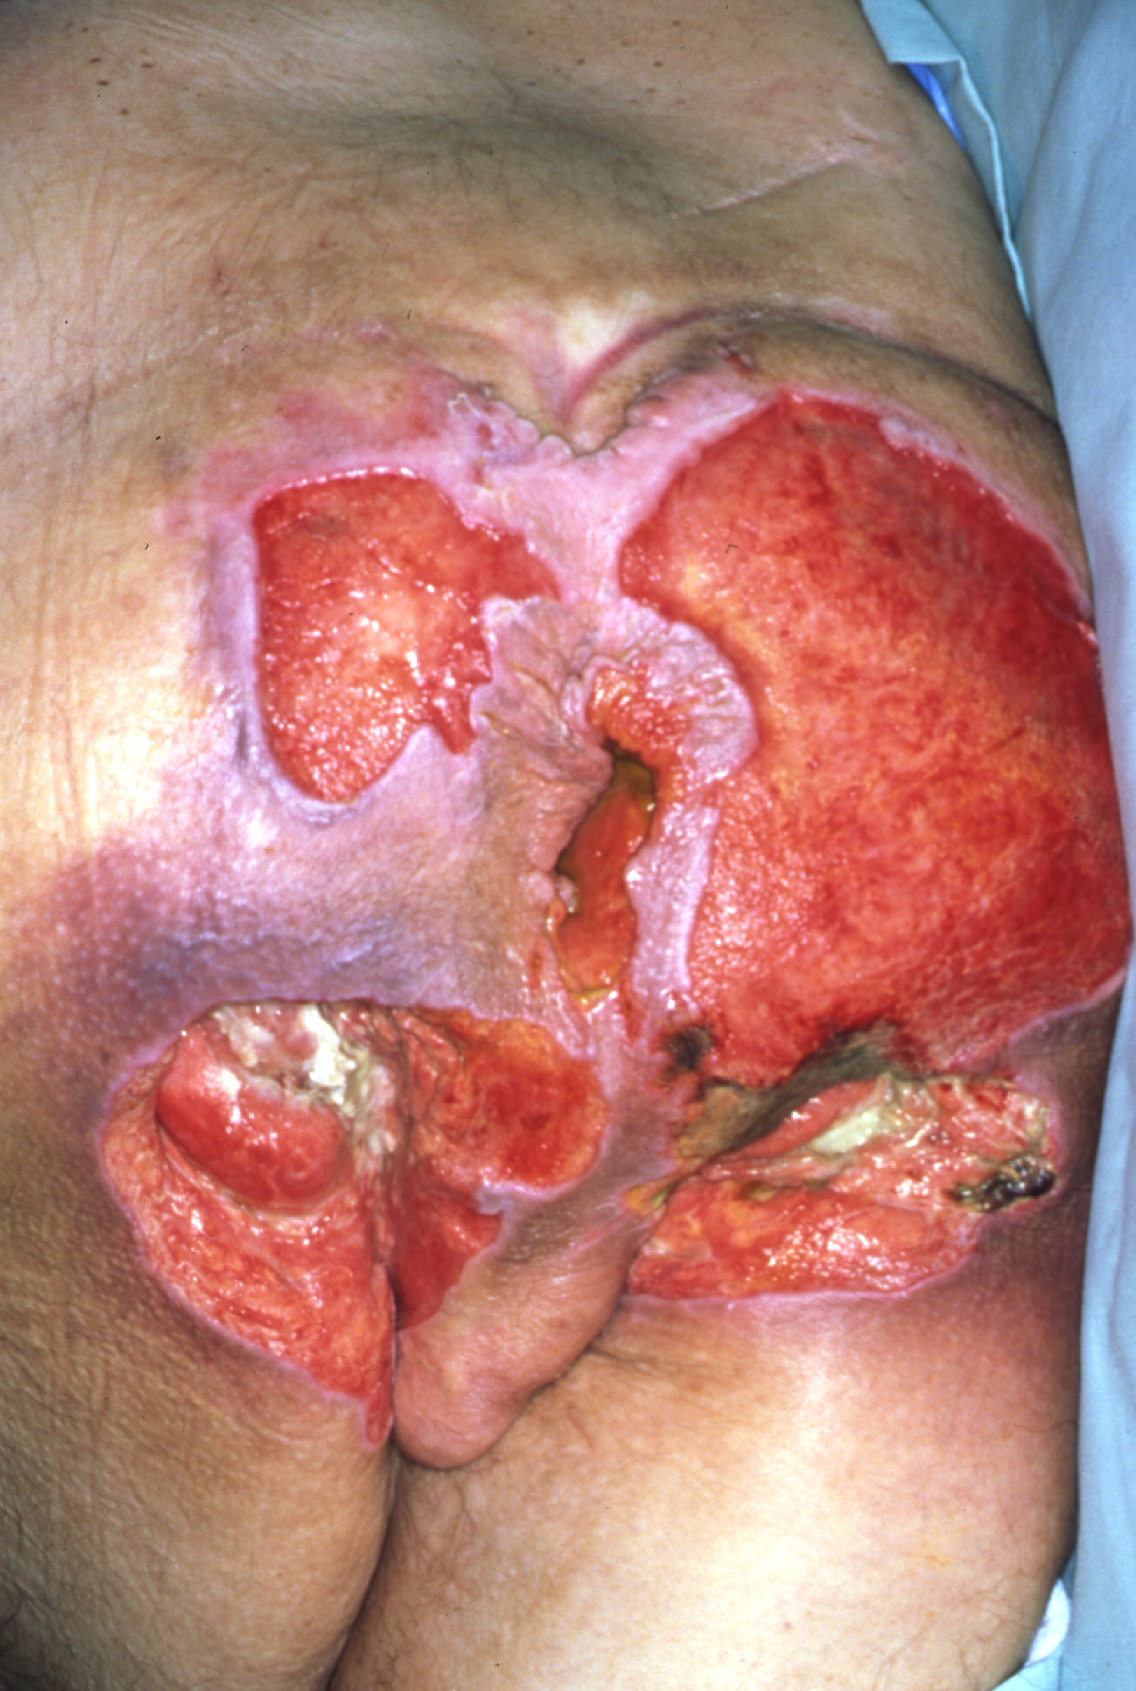

Stort tryksår i sæderegionen

Dybt tryksår på balden

Foto venligst udlånt af DermNet

• Kategori IV

• Sår gennem hele hudens tykkelse og med påvirket muskler og evt. knogle